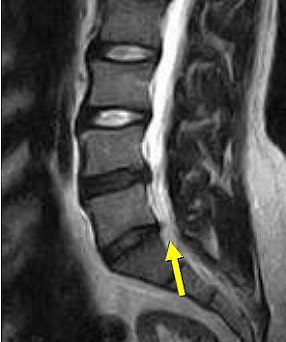

![]() |

| Above, nonaxial-loaded images. Below, axial-loaded images. Increase in stenosis at L4 level by 2.0 mm and left L4 spinal nerve root with axial loading. All images courtesy of Dr. Gerald Anzalone. |